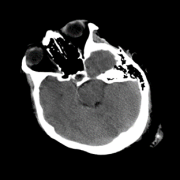

So far we have observed enhanced performance through the SA term. In this subsection, we visually illustrate how this novel term imposes smoothness between attention scores of consecutive slices, leading to more accurate predictions. Figure 2 shows plots of the attention scores assigned by SA-DMIL- and Att-MIL to the slices of three different scans (Fig. S1 in the appendix contains an analogous plot for SA-DMIL-). As expected, introducing the SA loss results in smoother attention weights. Note that the smoothness constraint of SA-DMIL effectively penalizes the appearance of isolated non-smooth attention weights that incorrectly jump over or below the threshold.

We also include visual examples of consecutive CT slices in Fig. 3. In Scan 1, the baseline Att-MIL produces a wrong prediction at scan level. When using SA, the prediction is correct since dependencies between adjacent slices have been learned. In Scan 2, both models produce correct predictions at scan level, but SA-DMIL is more accurate at slice level. This occurs thanks to the SA loss, that turns the attention scores into smoother values and, therefore, avoids random jumps up and down the decision threshold.